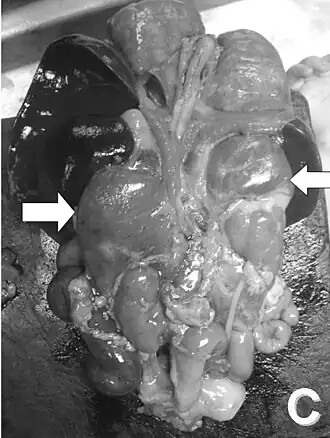

Exame de um bebê após sua morte. As setas indicam as supra-renais hiperplásicas.